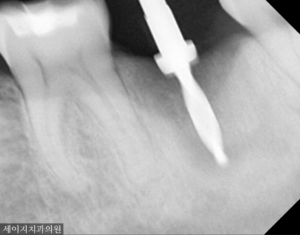

깨끗하게 치아를 제거하고 남아 있는 염증 조직을 소파하였습니다. 향후 임플란트가 채워질 자리이기 때문에 발치의 과정도 중요하지만, 남아있는 골조직에 염증이 잘 제거될 수 있도록 꼼꼼하게 제거해드렸습니다.

3개월 여의 시간을 기다려 잇몸이 아물고 뼈가 어느정도 회복할 시간을 기다려 임플란트 식립을 진행해드렸습니다.